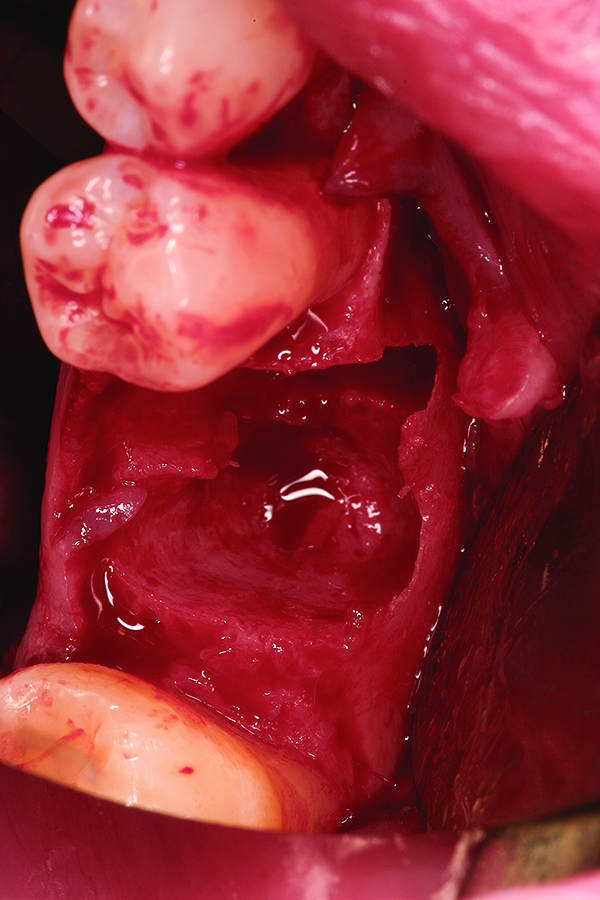

Fig 9. Note the significant osseous defect in the buccal osseous wall following atraumatic tooth extraction.

Figure 9